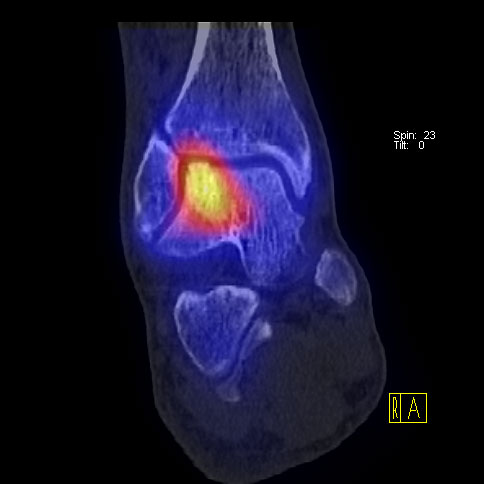

Die Kombination von SPECT und CT in einem Untersuchungsgang bringt wie bereits oben erwähnt eine erhöhte Ortsauflösung und artefaktfreie Darstellung von Knochenstoffwechselveränderungen der SPECT bei gleichzeitig excellent guter anatomischer Darstellung/Zuordnung durch die CT 3. Auf die Vorteile der CT gegenüber dem konventionellen Röntgen muss nicht mehr besonders eingegangen werden. Besonders eignet sich die „SPECT-CT“ zur Diagnostik von Fußerkrankungen (Biersack HJ et al. 2012).

Aufgrund der optimalen funktionellen Darstellung (PET) und der entsprechend guten anatomischen Bildgebung kann dieses kombinierte Untersuchungsverfahren viele Fragestellungen auch im Bereich des Fußes beantworten. Exemplarisch werden folgende Indikationen erwähnt. Abklärung von Infektionen im muskuloskelettalen Bereich 45, Untersuchungen von unklaren Fußschmerzen (Biersack HJ et al. 2012), präoperative Bildgebung beim Charcot-Fuß/diabetischer Fuß 31.